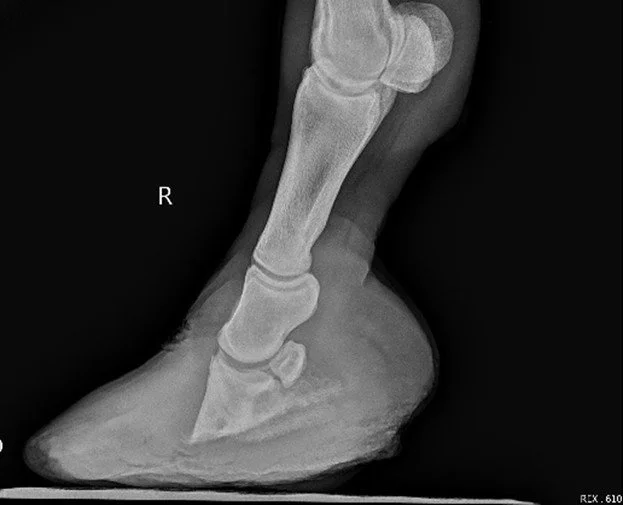

Divergent hoof rings showing previous laminitis

Laminitis is a painful condition affecting the structures that suspend the pedal bone inside the hoof.

When these attachments weaken, the pedal bone can rotate or sink within the hoof capsule, causing significant pain and long-term structural damage.

• Laminitis evaluation (often including radiographs)

Radiograph-guided trimming can greatly improve comfort, hoof mechanics and long-term outcomes.